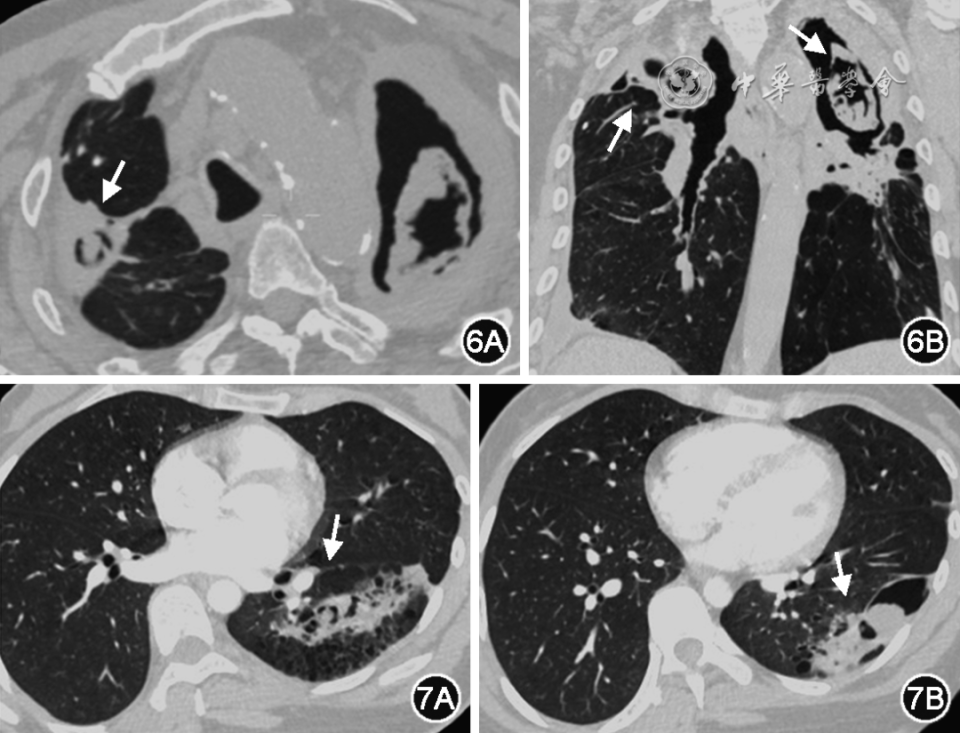

CCPA是慢阻肺合并CPA的最常见类型,在胸部CT上表现为多个或一个肺空洞/空腔结构,可含有一个或多个曲霉球或不规则内容物;常伴有临近胸膜的增厚。胸部影像可缓慢进展(图6)[48]。

图6 CCPA典型表现。患者,男,64岁,慢阻肺和陈旧结核病史,咳嗽加重半年伴消瘦。双肺上叶可见多发不规则空洞,空洞内可见曲霉球形成(白箭头)。双肺可见肺气肿改变

图7 SAIA典型表现。患者,男性,50岁,慢阻肺病史,反复咳嗽、咳痰伴发热2个月余。胸部CT显示左肺下叶不规则空洞,空洞内见球样结构,空洞周围肺组织实变(白箭头)

当患者免疫功能受损加重时,CCPA可演进为SAIA。SAIA也被称为半侵袭性(semi-invasive)肺曲霉病或CNPA。尽管在分类上属于CPA,但SAIA在病程和临床表现方面更倾向于IPA,以亚急性或慢性咳嗽、咳痰以及发热等全身症状为特征。15%的SAIA患者出现咯血症状。SAIA的影像表现多样,包括空洞、结节、进展性实变伴空洞形成,空洞周围可伴有实变、小叶核心结节,临近胸膜可见增厚,增强扫描曲霉球或内容物不强化,空洞壁可见强化(图7)。